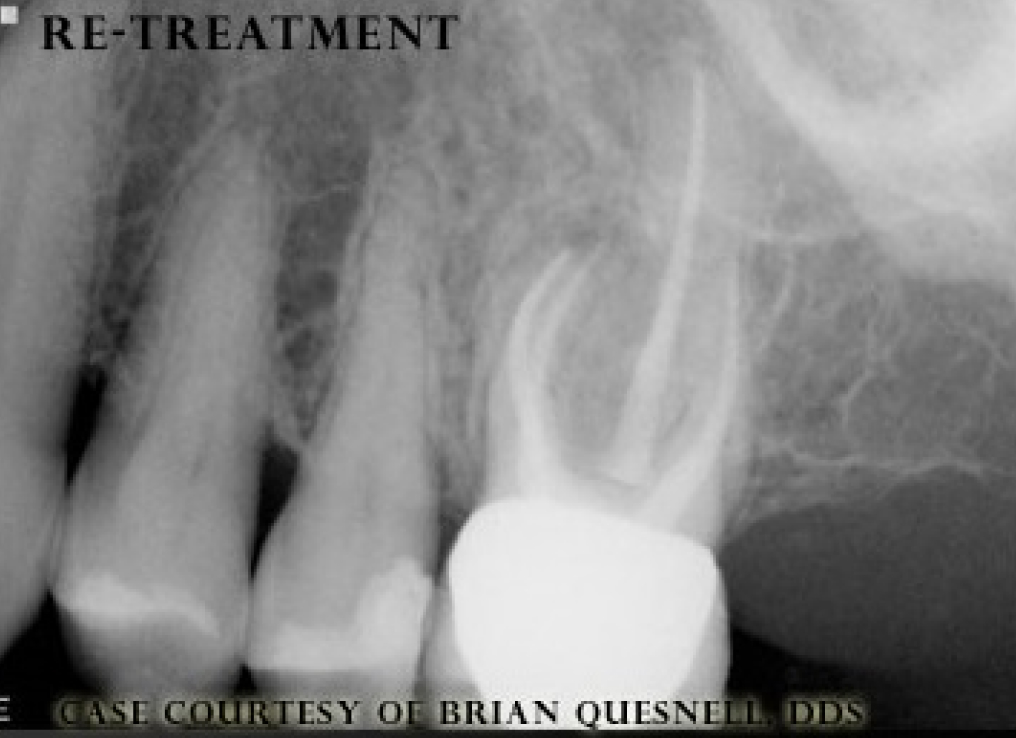

Case Study 6

Before

After